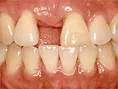

インプラント インプラントは第二の歯とも呼ばれ顎の骨に金属製のネジを立てて人工の歯を取付けます当院では高い技術と豊富な経験で対応しています 治療前

インプラントは第二の歯とも呼ばれ顎の骨に金属製のネジを立てて人工の歯を取付けます当院では高い技術と豊富な経験で対応しています 治療後

インプラントは第二の歯とも呼ばれ

顎の骨に金属製のネジを立てて

人工の歯を取付けます

当院では高い技術と経験で対応しています